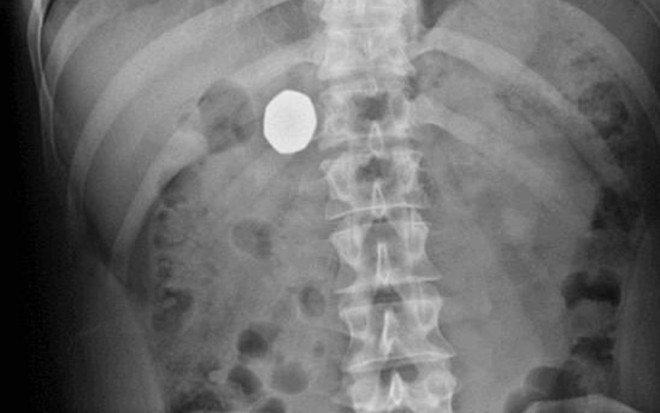

Um exame de raio x revelou que a moeda estava mesmo presa no corpo do rapaz

Os médicos pediram para que ele voltasse em uma semana e meia se ainda não tivesse conseguido se livrar do objeto. E foi exatamente o que aconteceu